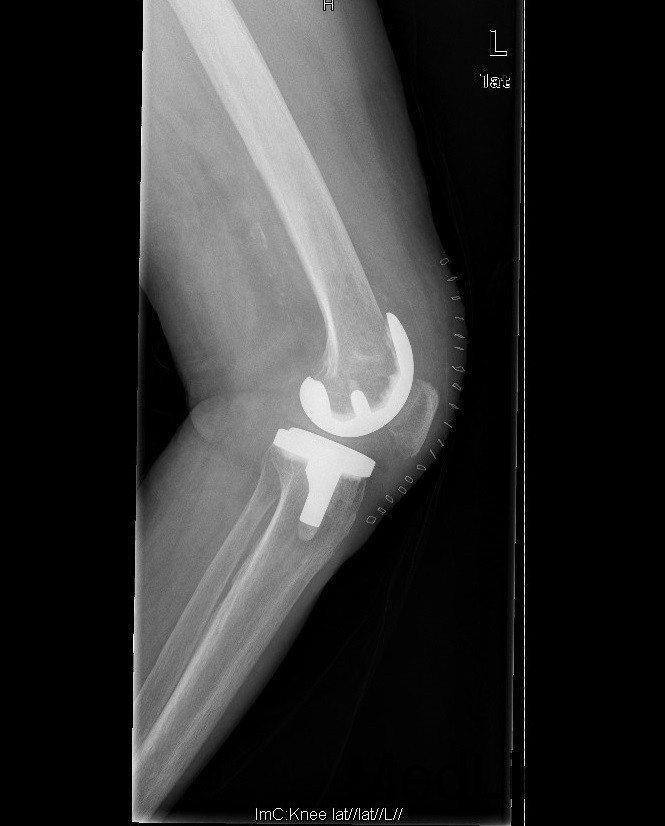

诊断:1、双膝骨关节炎伴屈曲内翻畸形 左侧重2、高血压病(2级高危、) 治疗:在全麻下行左侧全膝关节置换术+软组织松解术,术后予以抗炎+抗凝+镇痛+补液+护胃治疗,并指导其功能锻炼。

1、患者术后屈曲110°,伸0°,下地行走正常。 讨论 1、患者髌骨位置如何,术中有哪些方法避免术后低位髌骨 2、股骨曲度较大的患者,股骨截骨有何注意点